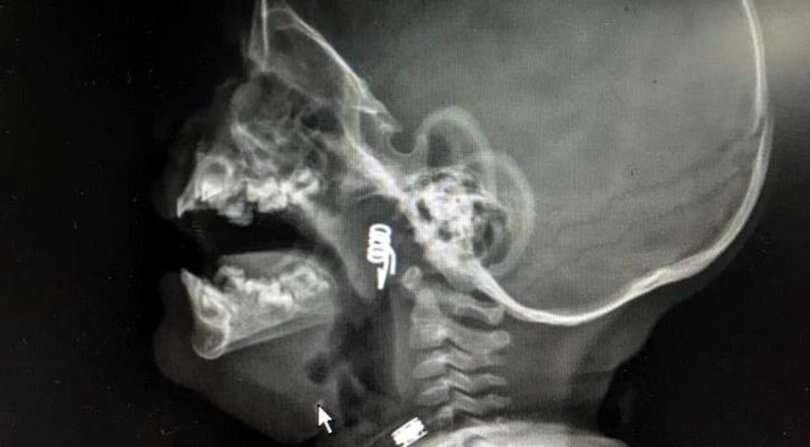

Nevşehir'de bir bebek oynadığı mandalın yayını yuttu.Hemen hastaneye kaldırılan bebeğin boğazındaki yay operasyonla çıkarıldı. Nevşehir'de 1 yaşındaki erkek bebek Ö.Y., dün akşam saatlerinde elinde mandalla oynarken, parçalanan mandalın yayını ağzına aldı. Durumu fark eden baba hemen müdahale etti ancak yay yay bebeğin genzine kaçarak saplandı. Bunun üzerine aile hemen hastanenin yolunu tuttu. Nevşehir Devlet Hastanesi Acil Polikliniği'ne getirilen bebeği, Acil Nöbetçi doktoru Mustafa Alpaslan muayene ederek gerekli tetkikleri yaptı. Çekilen röntgen filmlerinde mandal yayının lokalizasyonu ve durumu belirlendi. Daha sonra, KBB Uzmanı Op. Dr. Ahmet Cevatzade tarafından yapılan başarılı ameliyat sonucunda bebeğin genzine saplanan mandal yayı çıkartıldı.